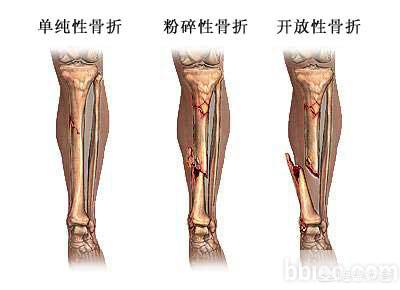

从广义来说的话,就是一个碗摔碎了与摔的粉碎。从医学的角度来说,就是骨的连续性与完整性中断,且骨折块大于3块以上,这就叫粉碎性骨折。

骨折可以分为很多种类型,而粉碎性骨折是我们所见到的最多的一种骨折。所谓粉碎性骨折是指骨头的完整性以及连续性遭受到破坏,是一种比较严重的骨折。

骨折一般分为线形骨折,错位骨折,还有粉碎性骨折。这几种骨折,以粉碎性骨折,最为严重。

骨折是各种原因导致的骨皮质的连续性和完整性中断,而粉碎性骨折就属于完全性骨折,是指骨质碎裂成三块以上。粉碎性骨折是非常严重的骨折,手术难度比较大。如果治疗不及时,手术不恰当容易遗留下问题。粉碎性骨折后遗症通常有以下几种情况:

粉碎性骨折,听起来貌似很严重的样子。其实也没有大家想象的碎成了渣渣那种样子。 只是从定义上来讲就是骨折后骨块大于等于3块以上统称为粉碎性骨折。

引起粉碎性骨折的主因主要有两个:1、直接暴力:骨折发生在暴力直接的部位。如打架、撞伤等。多为开放性骨折,软组织损伤常较重,一般直接就可以感觉的出来。2、间接暴力:是指骨折距暴力接触点较远,也即是不是直接引起的。大多为闭合骨折,软组织损伤较轻。如从楼梯上摔下来时,用手撑了一下,带来手腕的扭伤,引起的粉碎性骨折等。